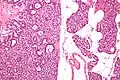

Micrographs